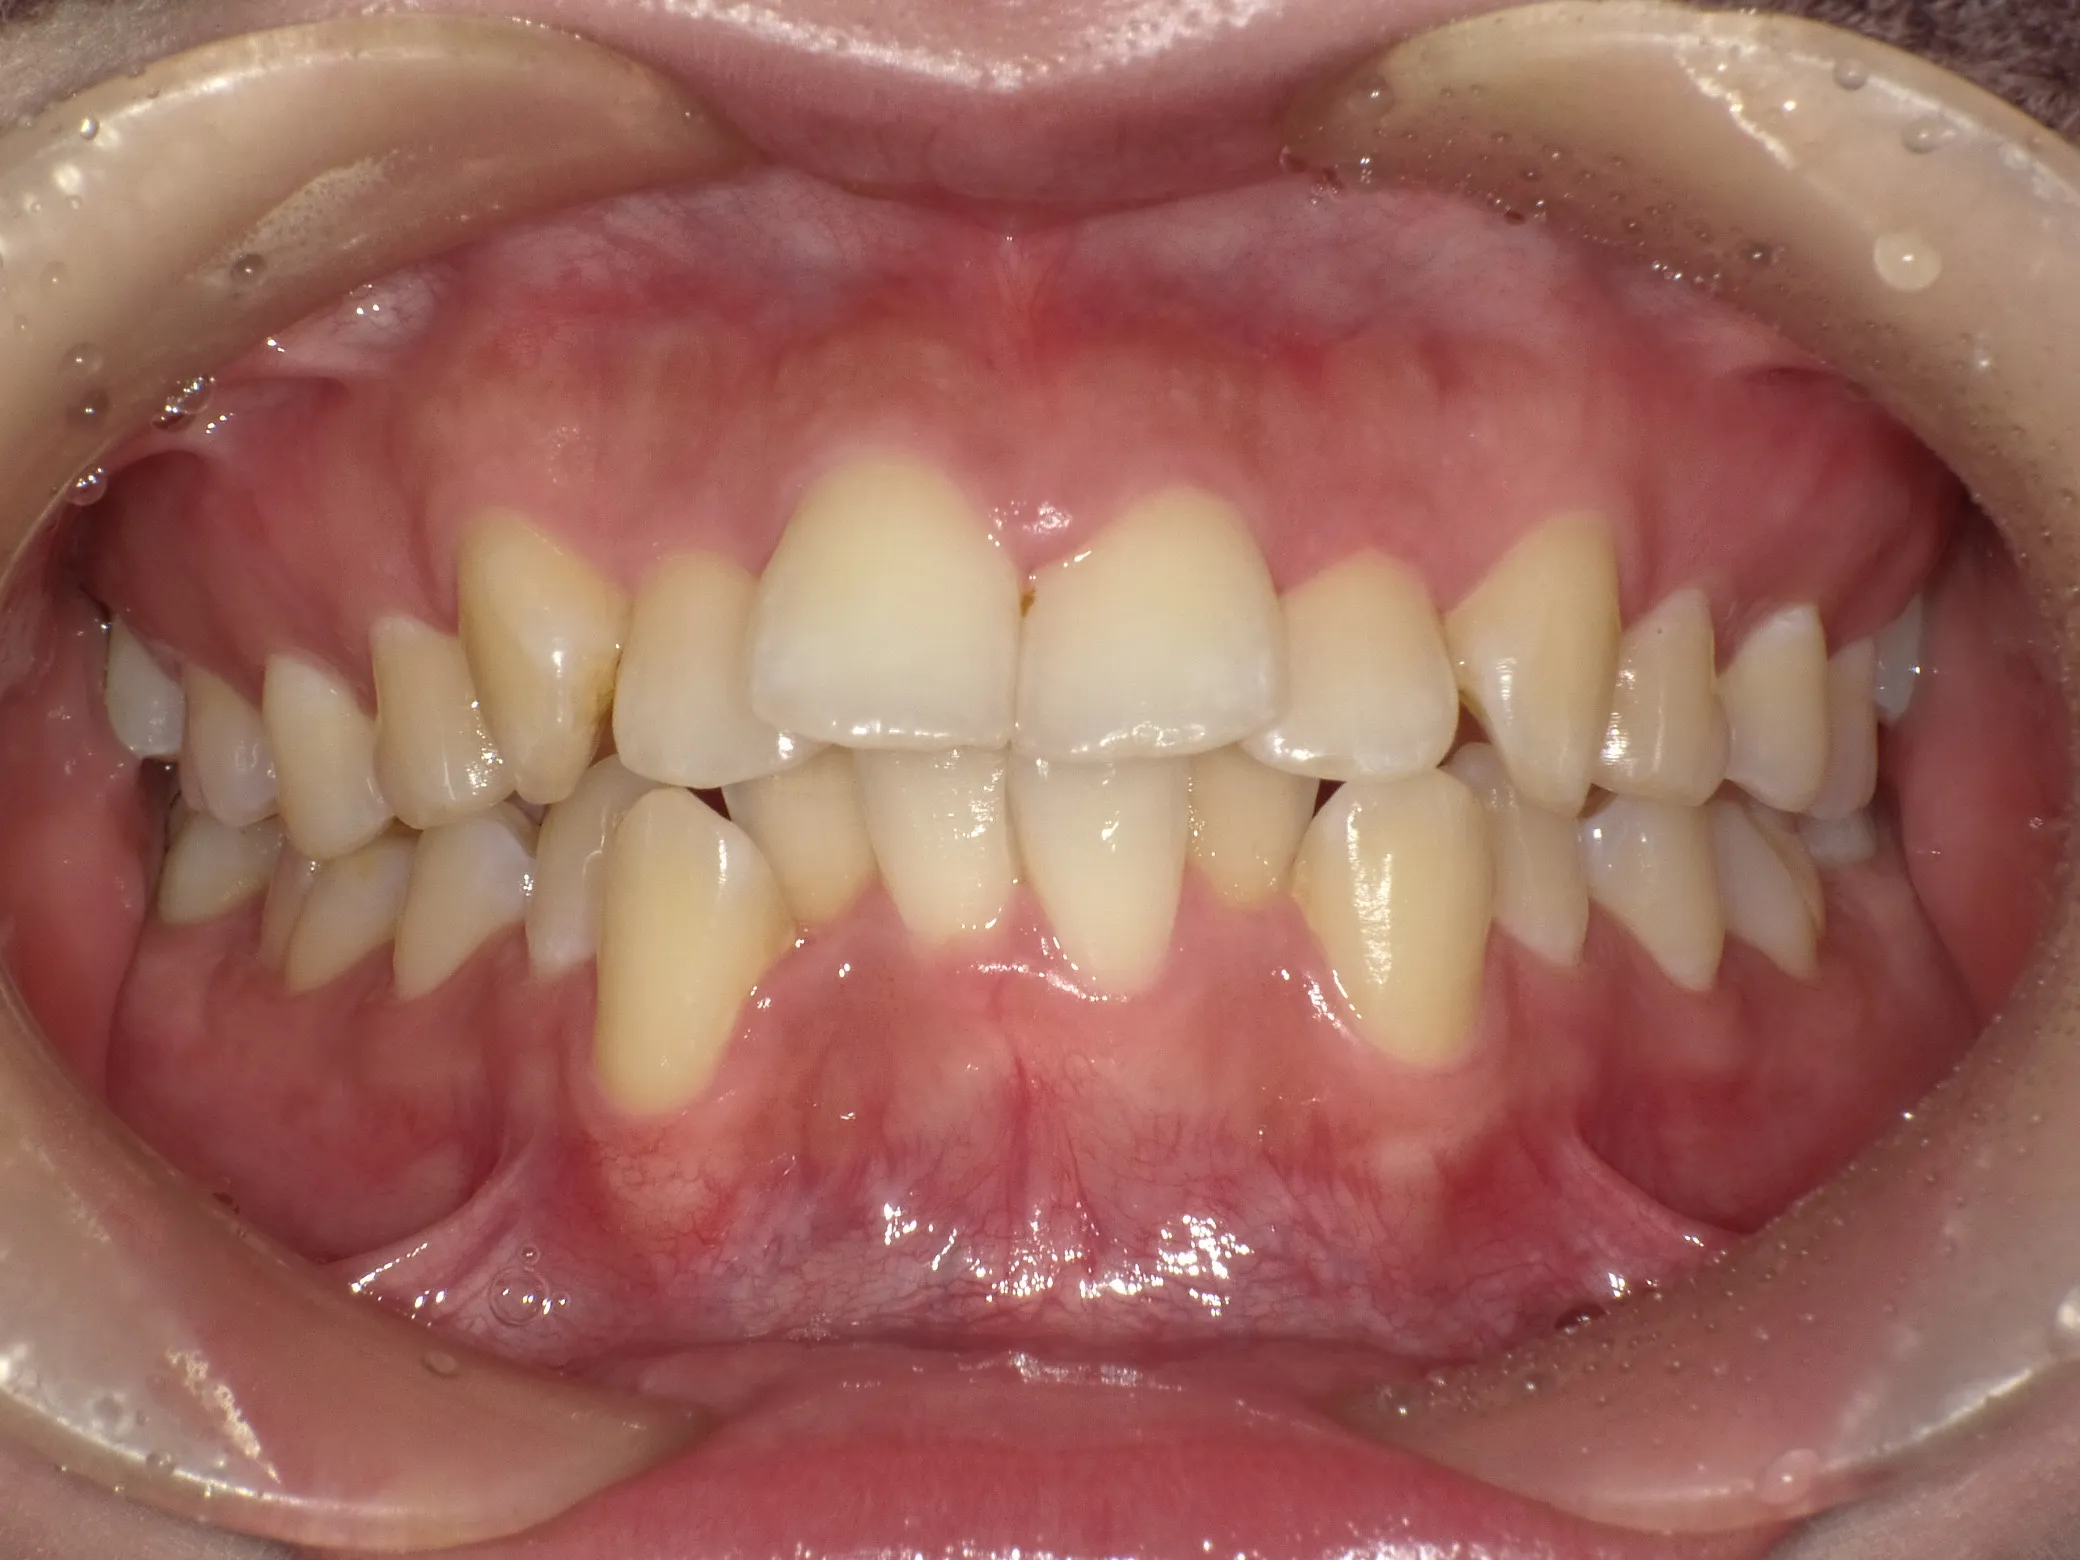

症例①

症例1_治療前 症例1_治療後

年齢(年代) 26才(当時)

治療方法 ホワイトブラケット

治療期間 3年

治療総額 825,000円

特記事項 抜歯あり